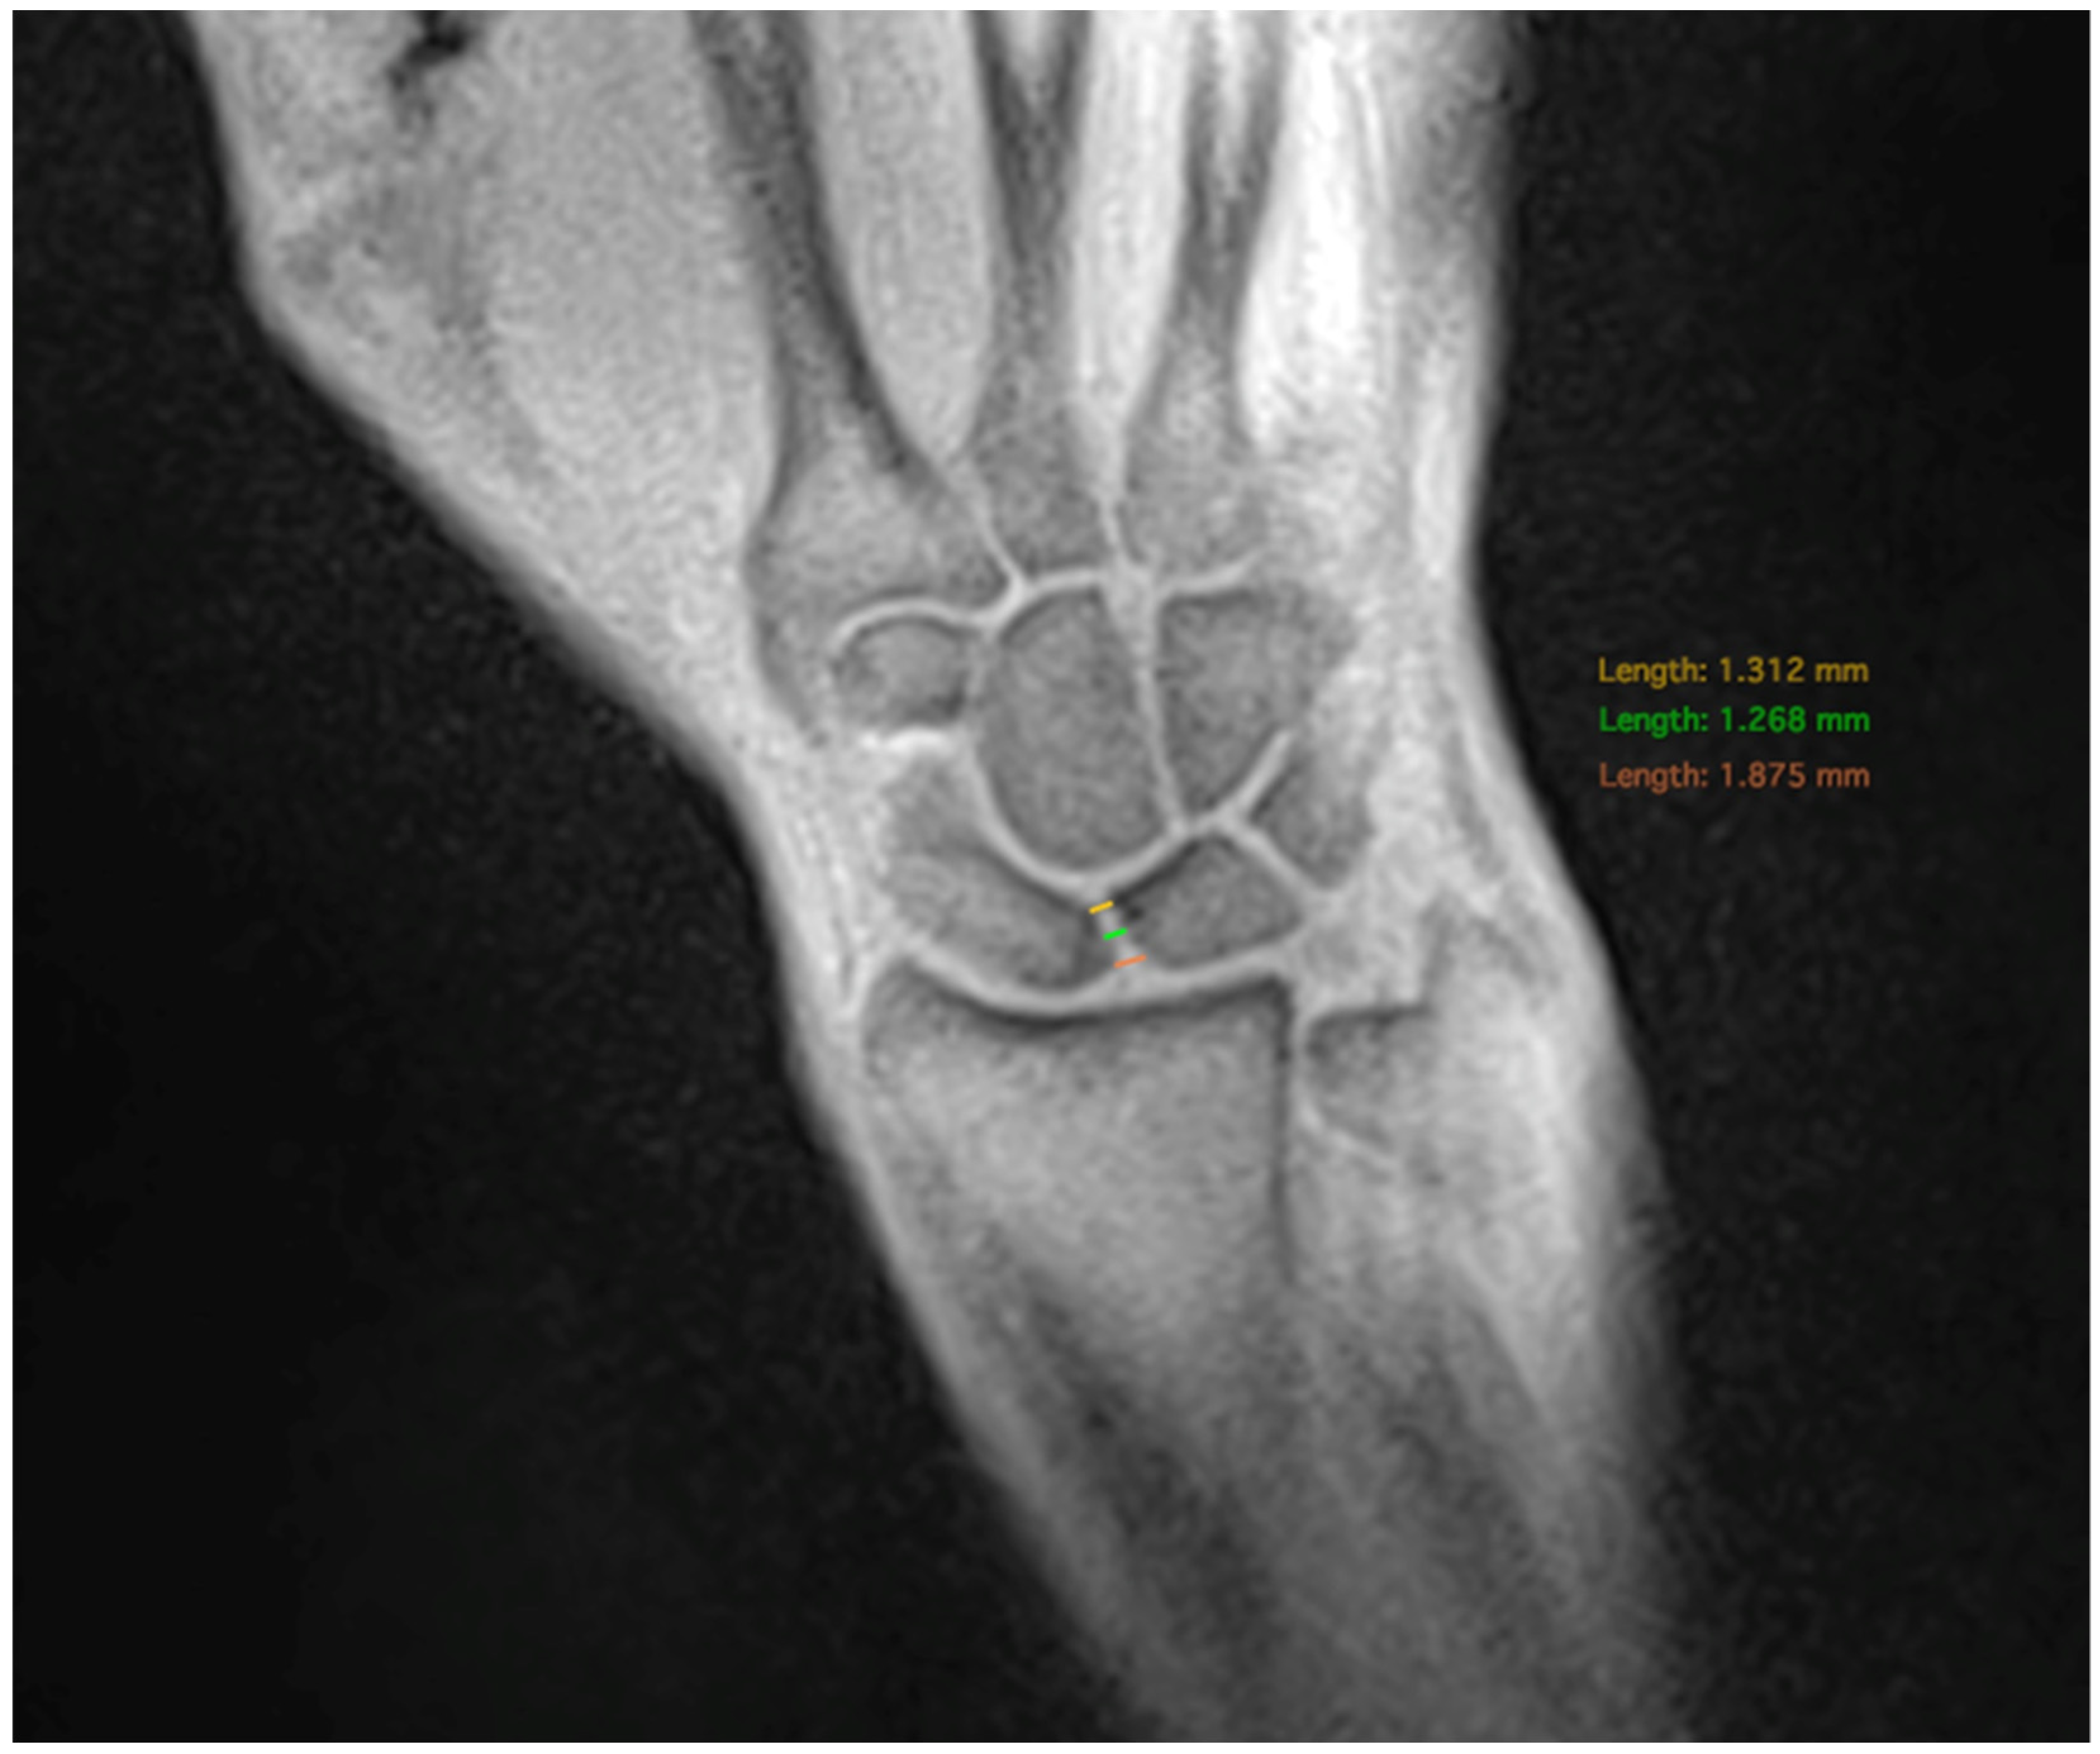

In the dynamic sequences, the SL width was determined every ten images. The extend and direction of movement in the radial or ulnar direction were determined by the angle formed between a line from the styloid process of the radius to the ulnar edge of the radius and the extension of the third metacarpal bone. The angle increased during ulnar movements and decreased during radial movements (Figure 3). The wrist angle remained constant during the fist clench maneuver and was therefore determined only once.

Figure 3. Measurement of the wrist angle determined by the extension of the third metacarpal and the distal radial joint line.